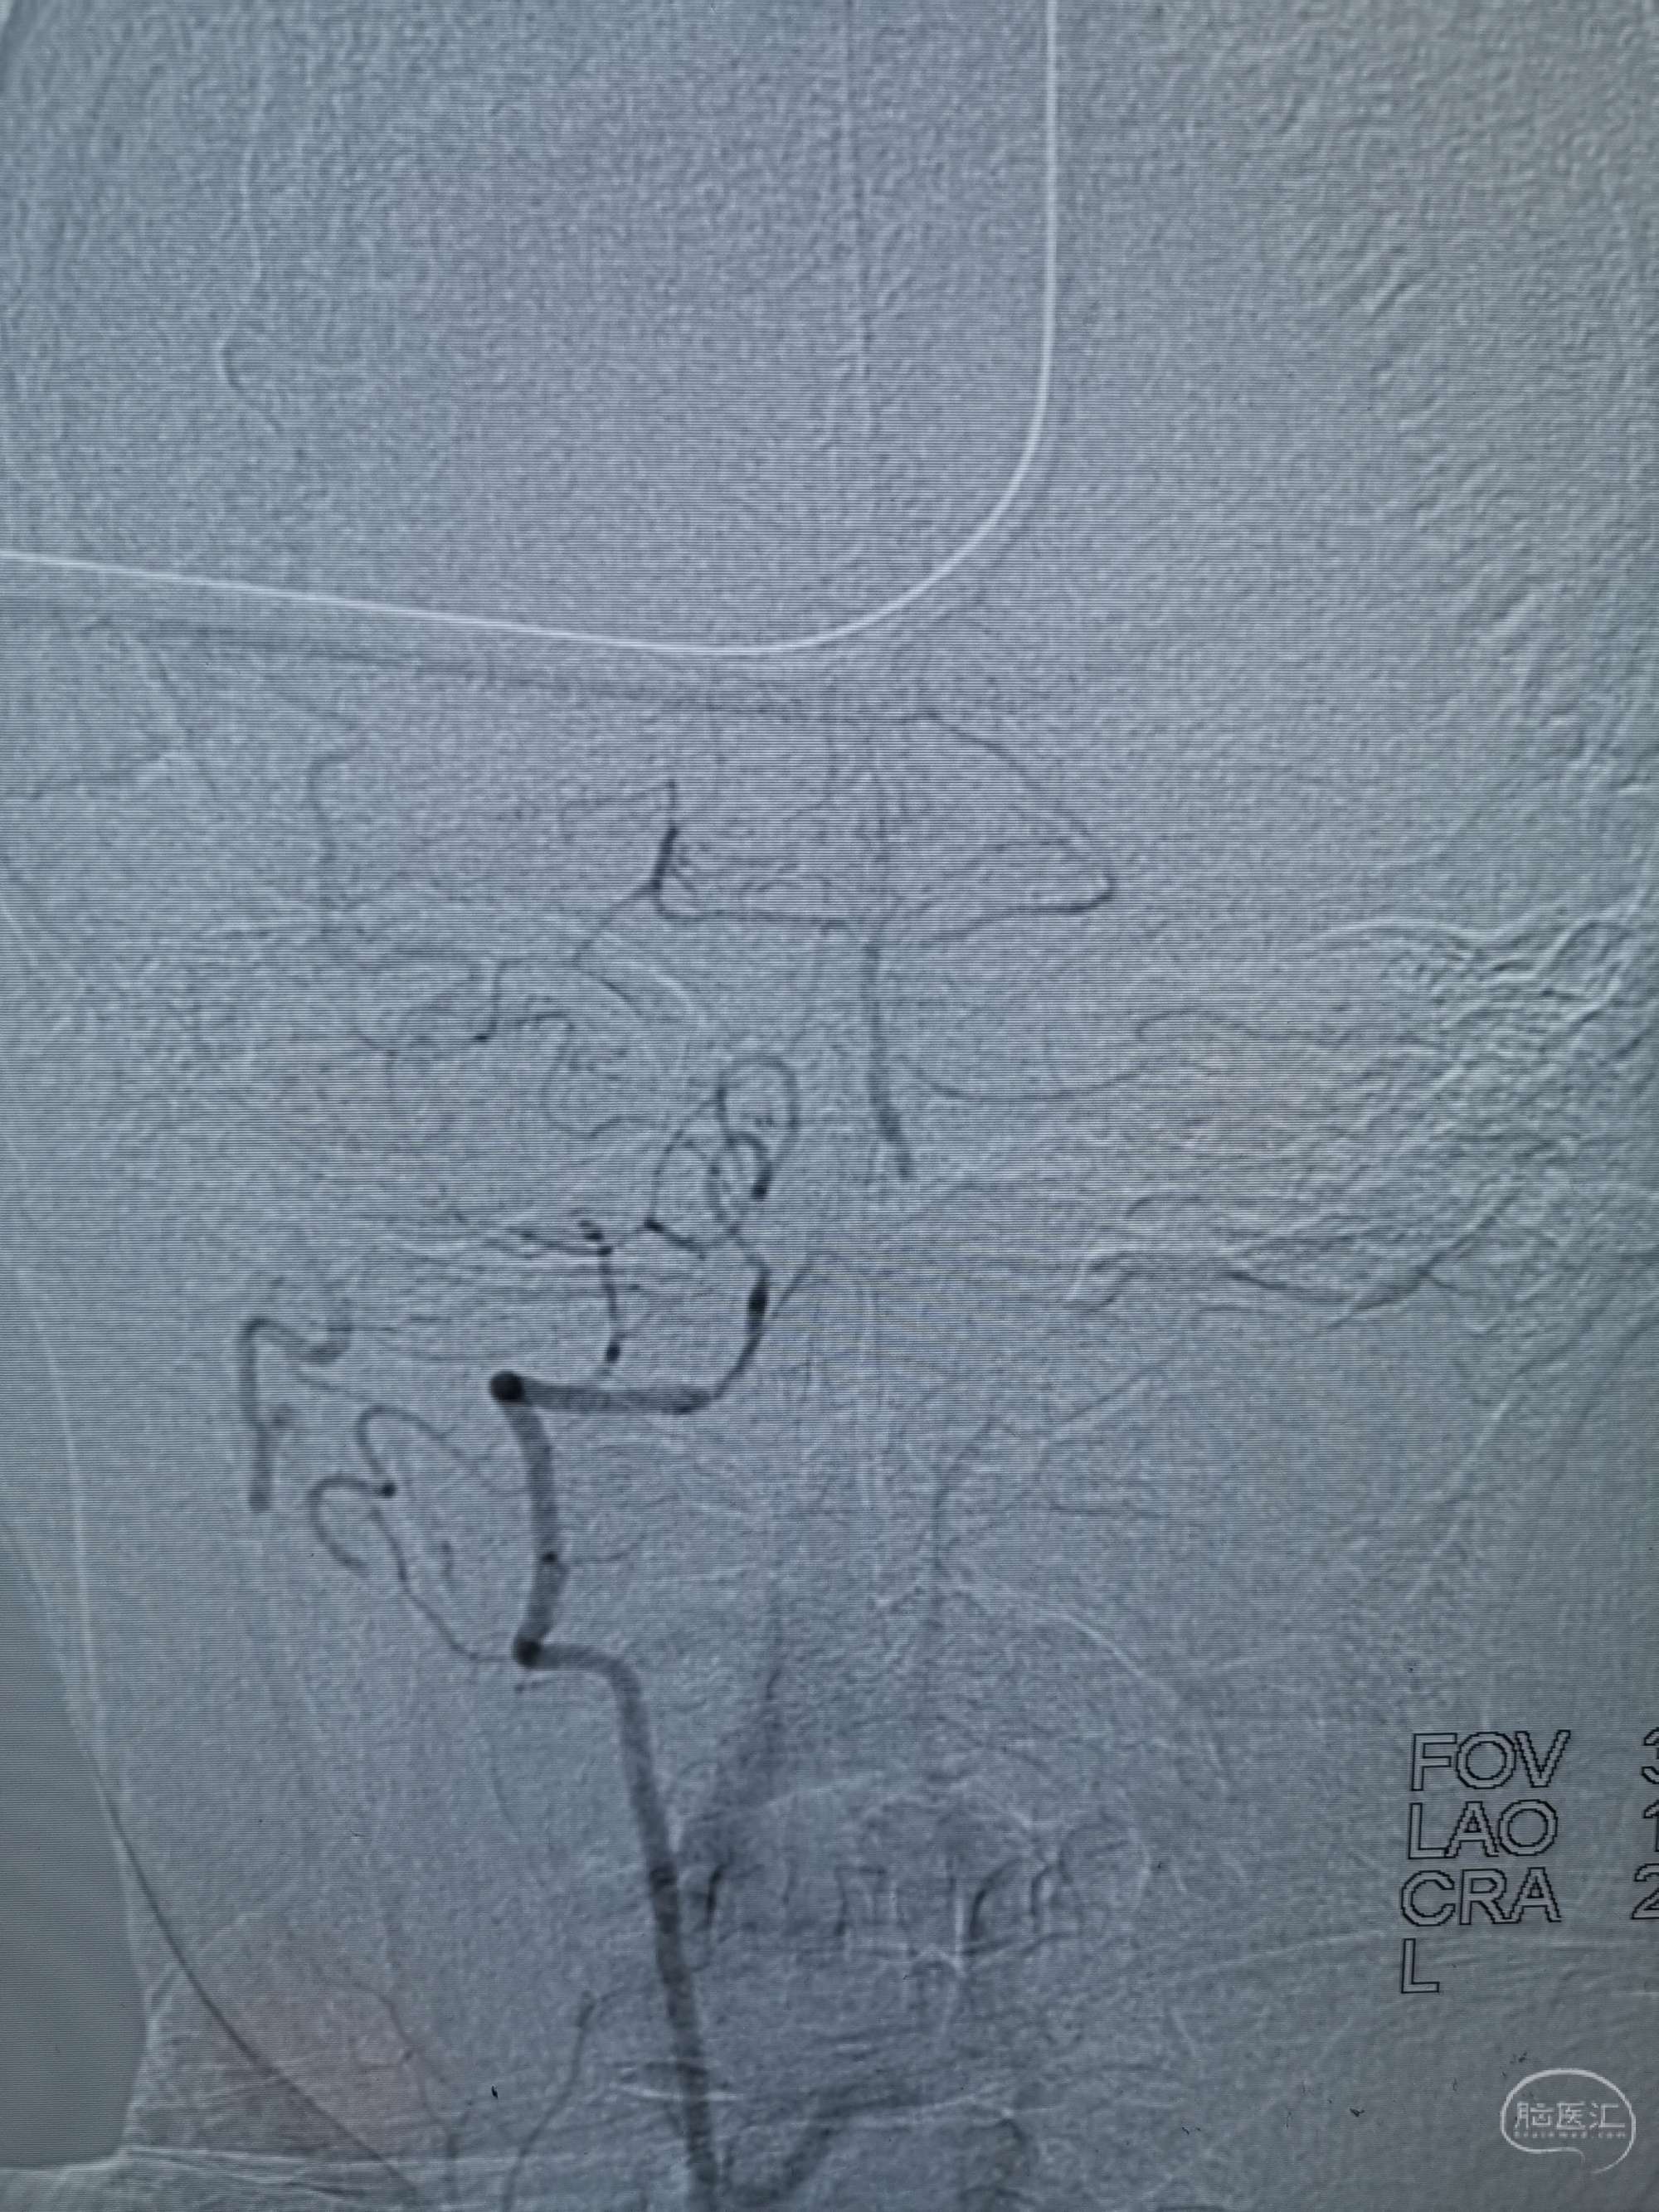

术前再次造影评估

右侧椎动脉穿支供血及左侧PICA供血较入院时略有改善,但改善不明显。故按计划行左侧椎动脉再通术